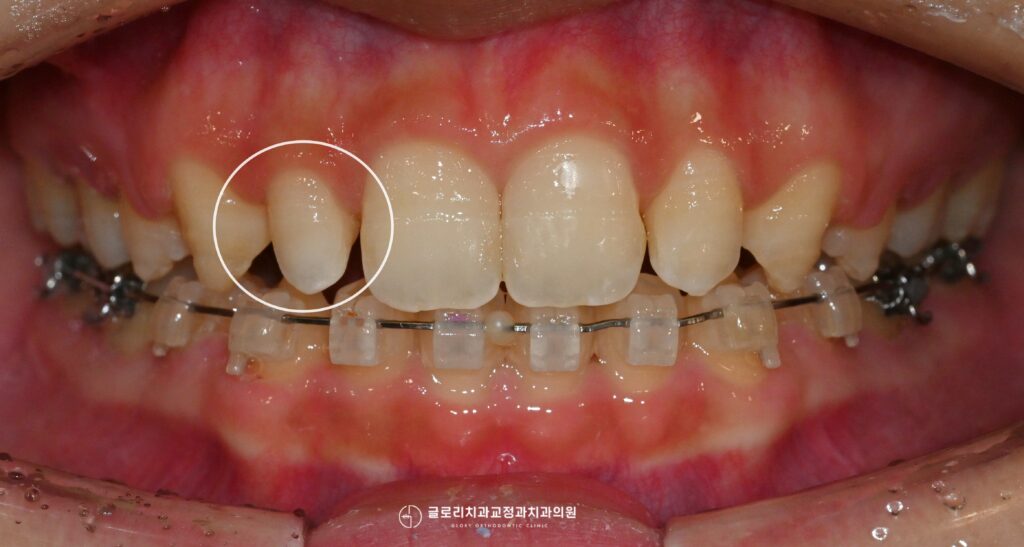

중랑구 교정치과 앞니가 삐뚤고 입이 나와보인다면? 발치교정을 통한 골격성 2급부정교합 개선 가능합니다.

안녕하세요, 교정과 전문의 김정은입니다. 앞니는 단순히 음식을 자르는 기능을 넘어 첫인상을 결정짓는 중요한 심미요소를 담당하는 부위입니다. 특히나 웃을때 제일 먼저…